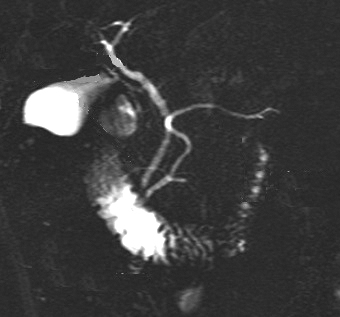

Image radiologique cholangio-

pancreatico par resonant magnetique ( CPRM ) du canal

pancreatiqur et des vois biliaire . La vesicule

biliaire etre en visible tres nette |

Apres injection de

Secretine **, la voie pancreatique et voie biliaire

avait une dilatation legerement du diametre et la dilatation maximale

etre entre 2 , 3 minute au debut de l'injection .

Image CPRM des canaux principales du pancreas et des

voies biliaires etre reconstructional en 3D .

Cette technique etre utilise

de diagnostique des lesions stenoses sclerosants ou des

infiltrants irreagularite du canal pancreatique |